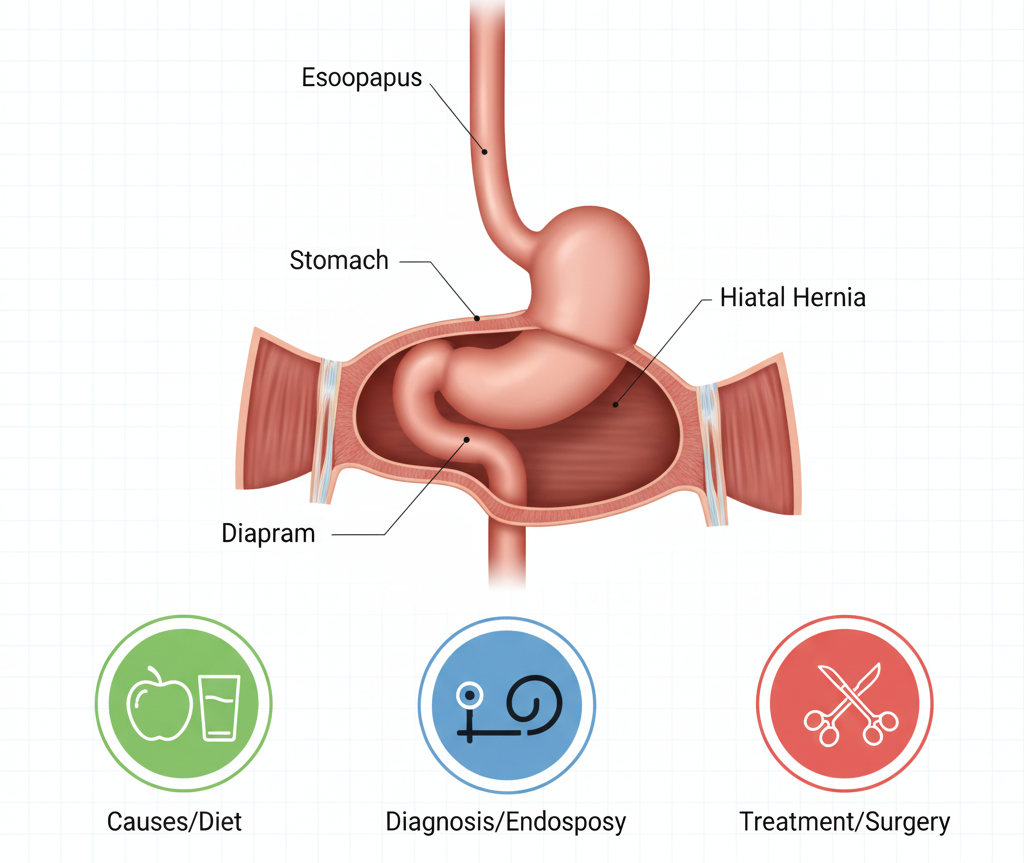

Hiatal Hernia for the Causes, Diagnosis, and Treatment Options

A hiatal hernia is a medical condition in which a portion of the stomach protrudes…